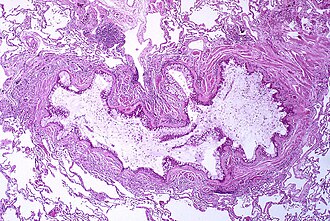

Astma nastaje uslijed kronične upale dišnih putova koja u konačnici dovodi do pojačanog stezanja glatkog mišićja u njihovoj stijenci. Ova je promjena jedan od čimbenika koji dovode do napada suženja dušnih putova i klasičnog simptoma zviždanja. Suženje je u tipičnim slučajevima reverziblino, uz liječenje i bez njega.U težim i kroničnim slučajevima dolazi do promjena u građi dišnih putova.[15] Tipične promjene su povećanje broja eozinofila i zadebljanje lamine reticularis u bazalnoj membrani epitela, a kasnije može doći do zadebljanja mišićnog sloja u stijenci uz povećanje broja žlijezda koje izlučuju sluz.Druge upalne stanice koje se također nalaze su: T limfociti, makrofazi i neutrofili. U reakciju mogu biti uključeni i drugi posrednici upale iz imunosnog sustava uključujući među ostalima i citokine, kemokine, histamin i leukotriene.[40]